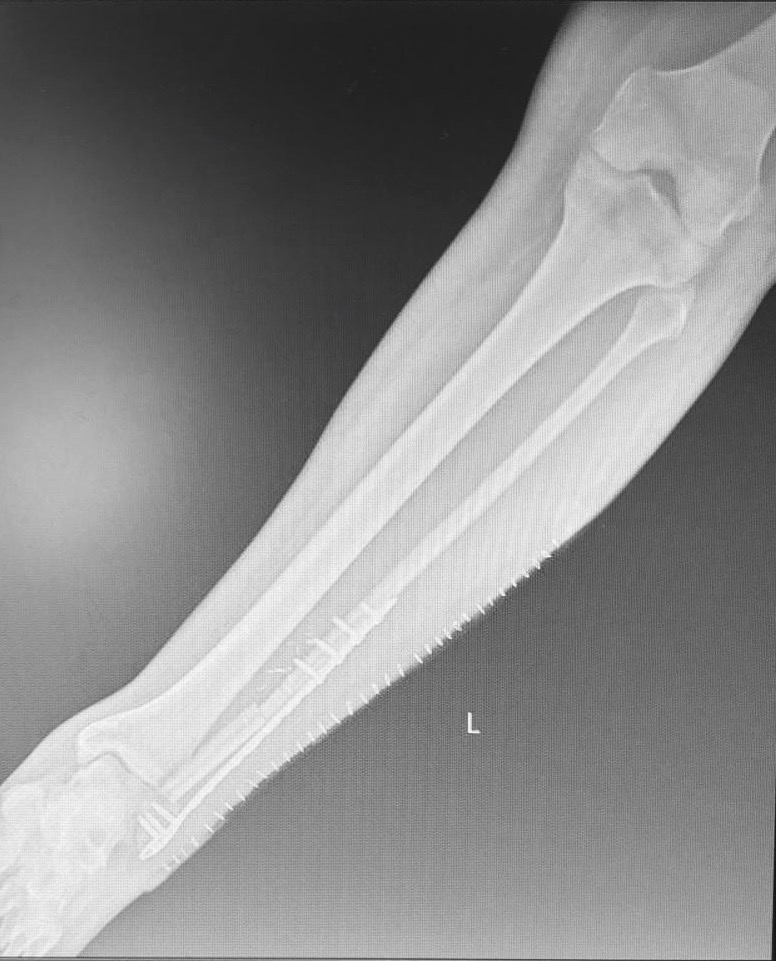

El paciente intervenido, de 49 años, estaba afectado por una fractura de peroné en la región de la articulación del tobillo, consecuencia de un accidente de tráfico hace ya 3 años, que no terminaba de evolucionar bien tras varias alternativas quirúrgicas. Así, tras apostar primero por fijar el hueso con placas y tornillos y posteriores injertos de hueso libre de la cadera, los focos de fractura seguían sin consolidar, por lo que, como recuerda la especialista, "el paciente sufría una importante inestabilidad en la función del tobillo y estaba sujeto a tratamiento con mórficos por mucho dolor en la pierna".

La tercera y última alternativa, nada menos que un trasplante microvascular del peroné de la otra pierna del paciente, ha supuesto un antes y un después en la resolución de este caso. Tanto que se ha traducido en un alta hospitalaria del paciente tras una evolución satisfactoria que le han permitido regresar a su domicilio tan solo con unas muletas y una sencilla pauta de tratamiento antiinflamatorio.

Una recuperación que el equipo del Dr. Alonso seguirá conforme a protocolo durante los próximos meses. Y un éxito que, en palabras de la Dra. Pingarrón, ha sido posible "gracias a un estudio y planificación tridimensional de la intervención previos a la misma mediante modelos estereolitográficos con el que los cirujanos pudieron identificar y programar las guías exactas de corte y diseñar el segmento preciso de peroné a trasplantar, y ante todo a la colaboración y trabajo en equipo".

Asimismo, y "dado que los vasos sanguíneos del peroné de la pierna afectada estaban muy deteriorados de cara a la anastomosis vascular por el tiempo transcurrido desde el accidente y los dos primeros abordajes quirúrgicos -continua la jefa del Servicio de Cirugía Oral y Maxilofacial del centro-, tuvimos que realizar una anastomosis término-lateral a los vasos tibiales para conectar extremos vasculares de diferente calibre, lo que terminó de consolidar el éxito de la intervención".

El resultado habla por sí solo: tan solo 24 horas de vigilancia intensiva en la UCI y una semana de ingreso hospitalario después de la intervención, el paciente ha sido dado de alta con un pronóstico favorable que confirma que la experiencia atesorada y compartida entre especialidades quirúrgicas -ambos servicios ya habían trabajado juntos previamente, en este caso con motivo de una fractura de antebrazo-, junto con la de la Unidad de Cuidados Intensivos y Anestesiología, sumado al enfoque multidisciplinar y personalizado de cada caso, pueden arrojar innovadores abordajes que redunden en claros beneficios para los pacientes.